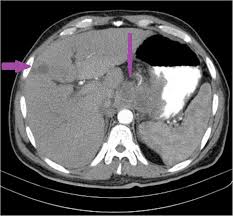

What Was Your First Sign Of Stomach Cancer : Stomach Cancer Possible Causes And Symptoms With Alternative Treatme : If you are experiencing any of these signs and symptoms, it is important to see your doctor.. Symptoms of early stomach cancer can be similar to the symptoms of other conditions, such as stomach ulcers. But in most cases, your pain is going to be the result of some other gut or abdominal ailment, not cancer, dr. Abdominal pain or discomfort above the navel may be a sign of a stomach tumor. The earlier we diagnose the cancer, the more successfully we can treat it. 9 jun 2019 14:45 in response to mikeswife.

Swelling and fluid build up in the abdomen also can be caused by stomach cancer. In fact, stomach cancer signs may be heartburn, indigestion, changes in appetite, nausea and vomiting. One of the early symptoms of stomach cancer is a pain in the stomach area or under the breastbone. The earlier we diagnose the cancer, the more successfully we can treat it. Or, the cause may be a different medical condition that is not cancer.

Stomach cancer, also known as gastric cancer, can affect any part of the stomach. Symptoms of advanced stomach cancer are more. Stomach cancer, in its early stages, rarely shows any warning signs or symptoms. According to the nci, around 30 percent of all people with stomach cancer survive at least five years after being. Pain in your stomach or breastbone. Stomach cancer is staged according to how far it has spread at the time of diagnosis. ) vomiting (the vomit may be streaked with blood), although this is uncommon in the early stages. They can affect your digestion, such as: Your chances of recovery are better if the diagnosis is made in the early stages. Heartburn or acid reflux having problems swallowing (dysphagia) When stomach cancer does cause signs and symptoms, they can include: There are many possible symptoms of stomach cancer, but they might be hard to spot. Pancreatic cancer is a tricky cancer to identify.

The cancer has not spread to lymph nodes or other tissues or organs, but has grown through the main muscle layer of the stomach wall into the subserosa (the thin layer between the main muscle layer of the stomach and the outside membrane of the stomach, called the serosa). The first signs of stomach cancer are often vague. That's why it is important that patients considered high risk talk to their doctors about. Your stomach receives and holds the food you eat and then helps to break down and digest it. You unexpectedly lose weight and your appetite plummets.